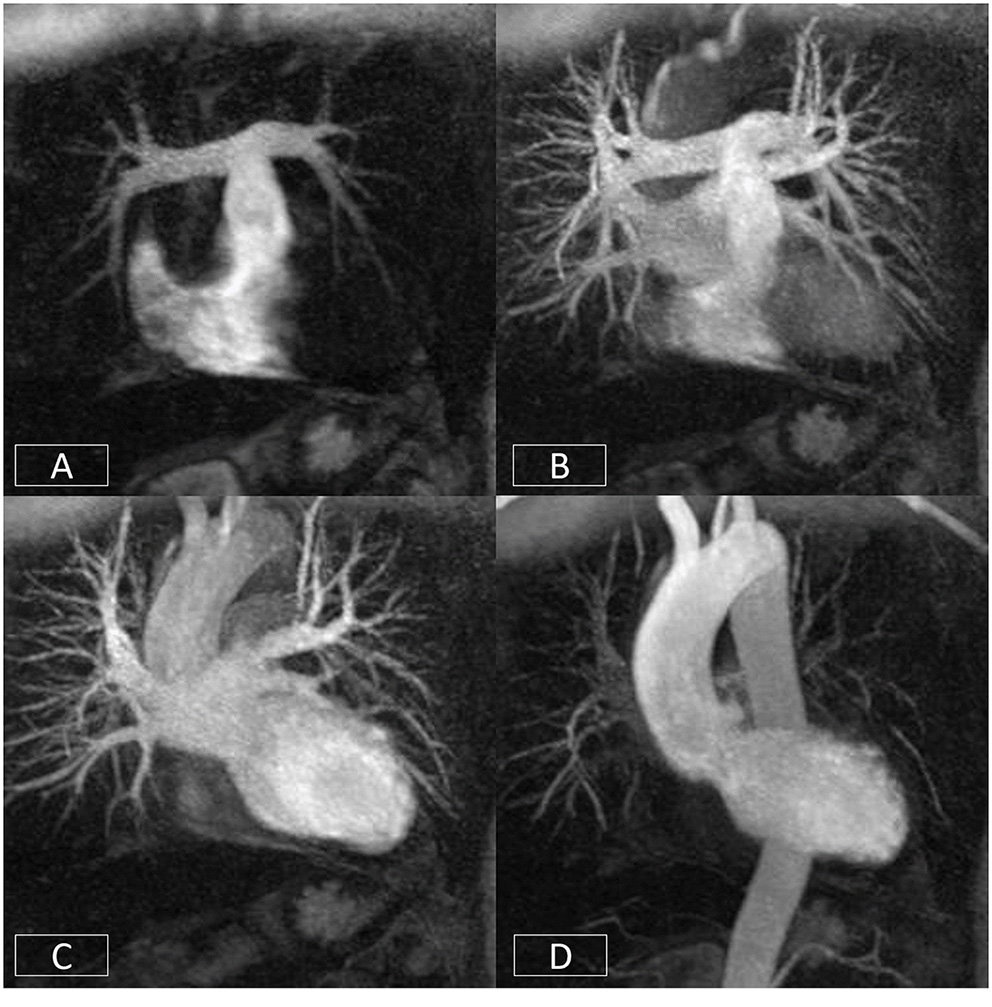

Figure 7

Cardiovascular time resolved 3D-angiography. The bolus of contrast is imaged progressively as it passes from the right side of the heart (A) into the pulmonary arteries (B), left atrium/ventricle (C), and thoracic aorta (D). This obviates the need to precisely time the contrast volume and enables the rapid visualization of different parts of the circulation with a single bolus of contrast.